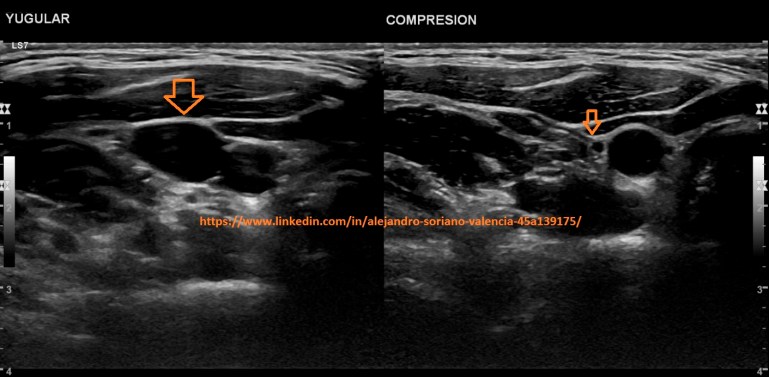

o Yugular interna.

Le pediremos al paciente que coloque el cuello en

hiperextensión para tener un buen acceso. La estudiaremos en su máximo

trayecto posible.

1. Yugular interna transversal.